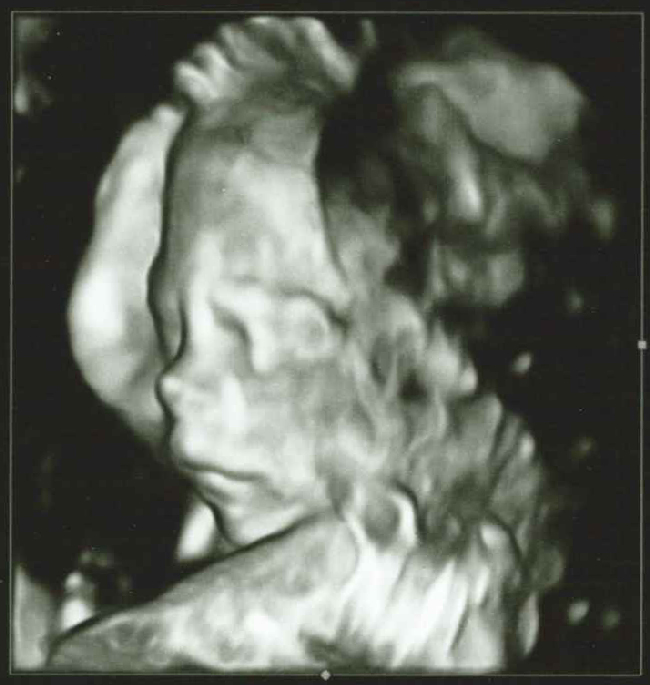

Gender reveal party